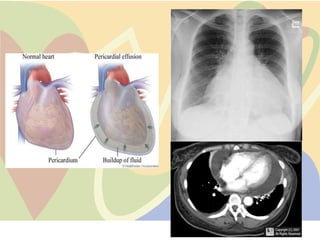

Pericardial effusion:

•          Accumulation of excess fluid in the

pericardial space.

•          When this obstructs the beating of

heart, it is termed cardiac tamponade.

•          Symptoms are severe edema, low

BP, shortness of breath, dizziness, chest

pain, cough, rapid pulse.

•          Causes are inflammation, rheumatoid

arthritis, surgery, cancer, infection, kidney

failure, hemorrhage, trauma or idiopathic.

•   Treatment: Giving NSAIDS, excess fluid drained

using a needle or in severe cases, surgery.